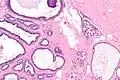

Collagenous spherulosis is characterized by a tubular/cribriform architecture with intratubular eosinophilic material that classically is arranged like the spokes of a wheel ("radial spikes"). There is usually no mitotic activity, and two cells populations (epithelial & myoepithelial) are present, like in benign breast glands.

The lesions are typically small (less than 50 spherules per lesion, less than 100 micrometers in size) and may be multifocal.

High mag.